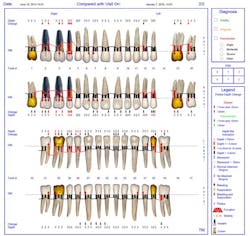

This patient had with a noncontributory medical history. Implants were placed in the upper right maxillary quadrant in 2006, and the patient came in for six-month recare visits. Ideally, he would have regularly alternated between the periodontist and the general dentist for care, but the patient elected only to be treated for maintenance intervals at the general dentist’s office. Significant bleeding and pocketing around the implants was noted eight years later in 2014, but there was no radiographic evidence of bone loss. (figures 1 and 1a).

Tray delivery, four times daily for 15 minutes, began on August 21, 2014, for the first two weeks, and then two times a day for 15 minutes for the duration of treatment. Debridement, laser therapy, and subgingival irrigation were completed between September 9 and November 13, 2014. The patient continued to use the trays in maintenance therapy two times a day. At the February 20, 2015, maintenance visit, all pockets were within normal range except for four 4 mm pockets (figure 3). There was no bleeding, and a secondary diagnostic test confirmed a reduction in pathogenic oral bacteria.